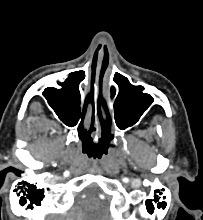

Одним из методов диагностики заболеваний носоглоточной области является мультиспиральная компьютерная томография. Методика предусматривает использование рентгеновского излучения. Благодаря различной способности тканей поглощать рентгеновские лучи и последующей цифровой обработке полученных данных, удается получить изображения исследуемой зоны в мельчайших подробностях. Рентгеновские лучи лучше всего поглощаются плотными тканями, такими как костная ткань, поэтому кости хорошо видны на снимках КТ.

При необходимости улучшения визуализации мягкотканных структур и особенно при подозрении на опухолевый процесс, применяется внутривенное болюсное контрастирование. Йодсодержащее контрастное вещество вводится пациенту в вену, после чего оно попадает в кровеносную систему и с током крови разносится по организму. Патологические очаги в большей степени накапливают контраст, что на снимках придает им детальность и яркие очертания на фоне окружающих здоровых тканей.

Инновационные цифровые приложения томографов позволяют получить снимки высокого качества и детализации, а также создать трехмерные реконструкции анатомической зоны исследования, что дает возможность рассмотреть пространственное расположение органов и патологических образований. КТ носоглотки с контрастом назначают при подозрении на рост новообразований, в случае хронического воспаления, при врожденных аномалиях строения носа и прилегающих к нему придаточных пазух.